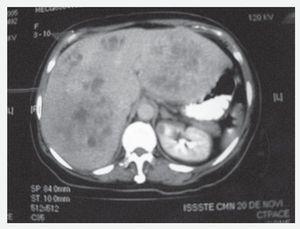

Resumen clínico. Femenino de 51 años de edad, con dolor abdominal de 3 años de evolución en cuadrante superior derecho, náusea, vómito, diarrea, diaforesis, palpitaciones y enrojecimiento facial. La tomografía axial (Figuras 1 y 2), mostró múltiples masas en ambos lóbulos del hígado; los niveles urinarios de ácido 5-hidroxiindolacético fueron normales. Se diagnosticó TCMH basado en octreótide marcado con Indio 111 (Figura 3), laparotomía exploradora sin encontrarse lesión primaria y la biopsia hepática, con tinción de grimelius y cromogranina A positiva para tumor carcinoide (Figura 4). La paciente recibió octreotide LAR controlándose los síntomas de síndrome carcinoide, y posteriormente fue sometida a hemipatectomía izquierda. Actualmente, se encuentra en control de su sintomatología con octreótide LAR y en lista de espera de trasplante hepático de donador cadavérico.

Figura 2. Hepatomegalia con lesiones multicéntricas bilobulares.